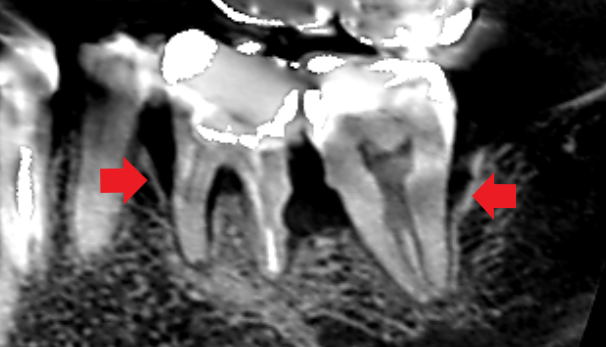

マイクロスコープ歯周再生療法を行ったケース。歯の周囲の骨が回復している。